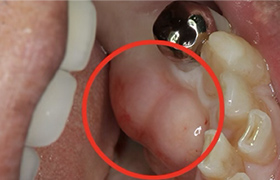

歯牙移植(骨の移植)

むし歯や歯周病で歯を失った後に、通常必要のない親知らずを、なくなった箇所に移植することによって健康な歯並びを回復する事ができます。

※移植には適合のための条件があります。